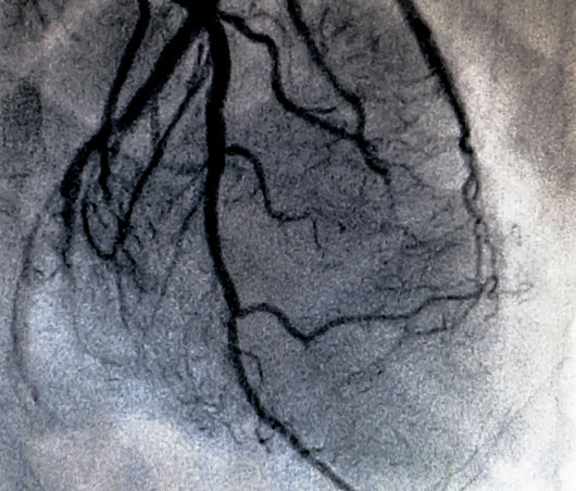

Хірург транскутанно виконує пункцію радіальної артерії чи загально-стегнової артерії, за допомогою гідрофільного провідника діаметром 0,035’’ вводить діагностичний катетер PigTail в цільову зону дослідження. За допомогою діагностичного катетеру та шприця-інжектора хірург виконує селективну ангіографію цільового артеріального басейну та камер серця. Дослідження виконується під контролем рентгеноскопії та рентгенографії у різних проекціях. Після виконання дослідження хірургічний інструментарій видаляється та виконується гемостаз судинного доступа.